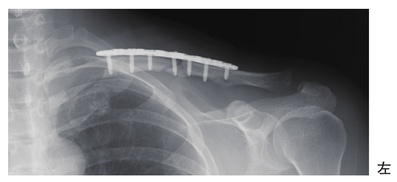

68歳の女性。外出中、前方に転倒して受傷し、骨折に対して手術療法が行われた。術後のエックス線写真を別に示す。手術後の理学療法で正しいのはどれか。

53歳の女性。自転車走行中に転倒受傷し、鎖骨骨幹部骨折に対して観血的整復固定術が施行された。術後のエックス線写真を別に示す。術後翌日の患側の理学療法で正しいのはどれか。